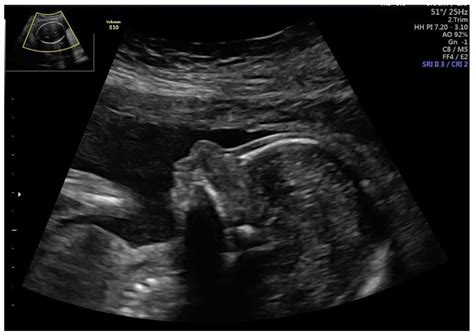

During the first and second trimesters, doctors look for specific anatomical findings. The most well-known screening takes place between 11 and 14 weeks of gestation, known as the Nuchal Translucency (NT) scan. Here are some of the markers that clinicians pay close attention to:

• Nasal Bone: The absence or hypoplasia (underdevelopment) of the nasal bone is often assessed during the first-trimester scan.

• Shortened Limb Bones: Sometimes, the humerus (upper arm bone) or femur (thigh bone) may measure slightly shorter than the gestational age suggests.